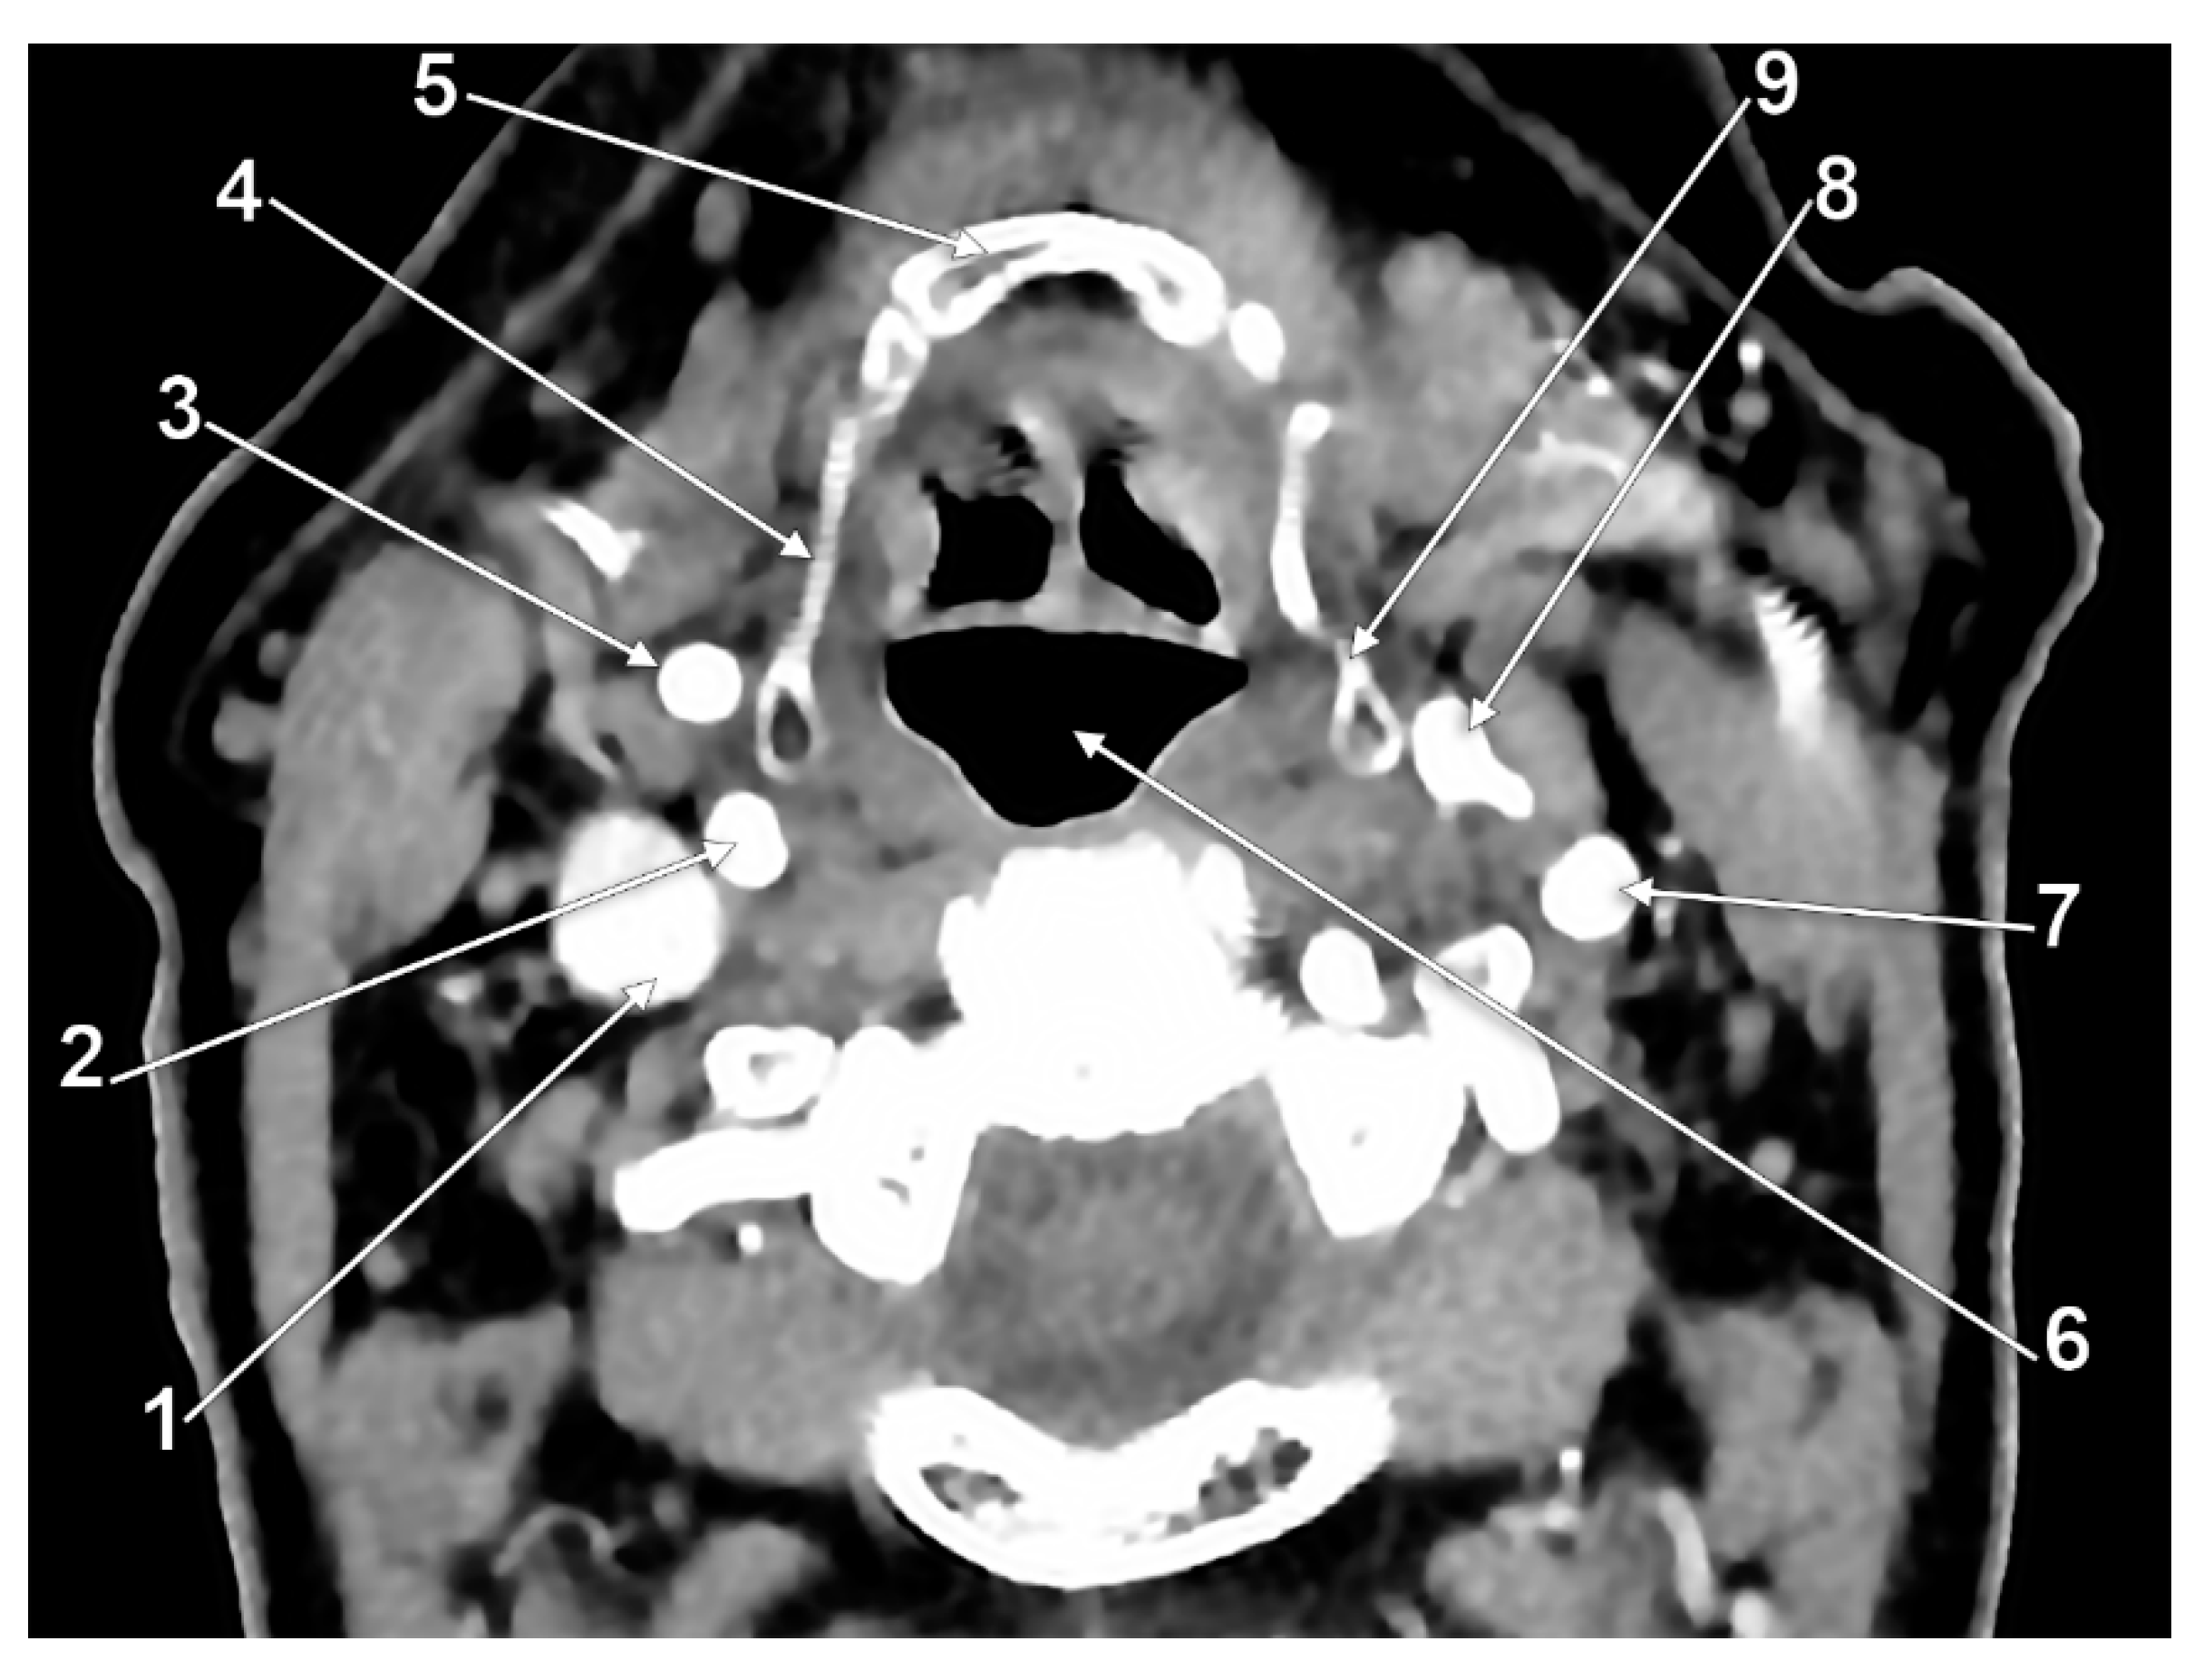

3. Results